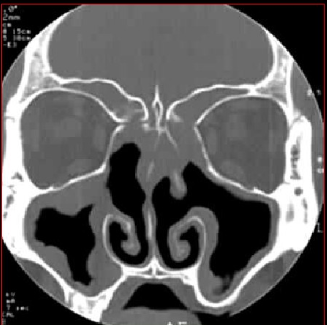

急性鼻窦炎